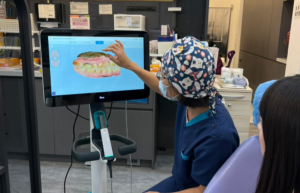

圖:黃汝萍醫師為患者解說隱形矯正口掃影像 世界人口邁向高齡化,全球世衛組織及先進國家都在提倡「8020口腔保健計畫」,意謂讓80歲以上長者能保留20顆以上的自